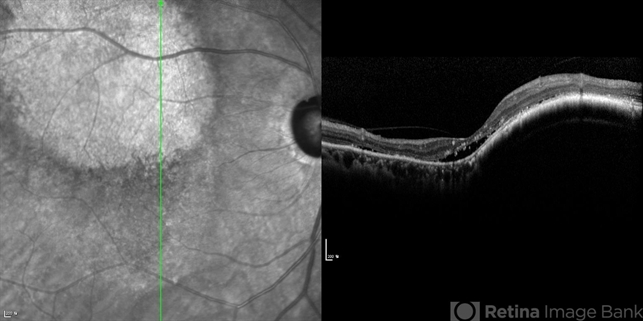

- Fundus and OCT examination showed an oval mass at the posterior pole with indistinct margins that blend with surrounding choroid. FA early phase showed hyperfluorescence.